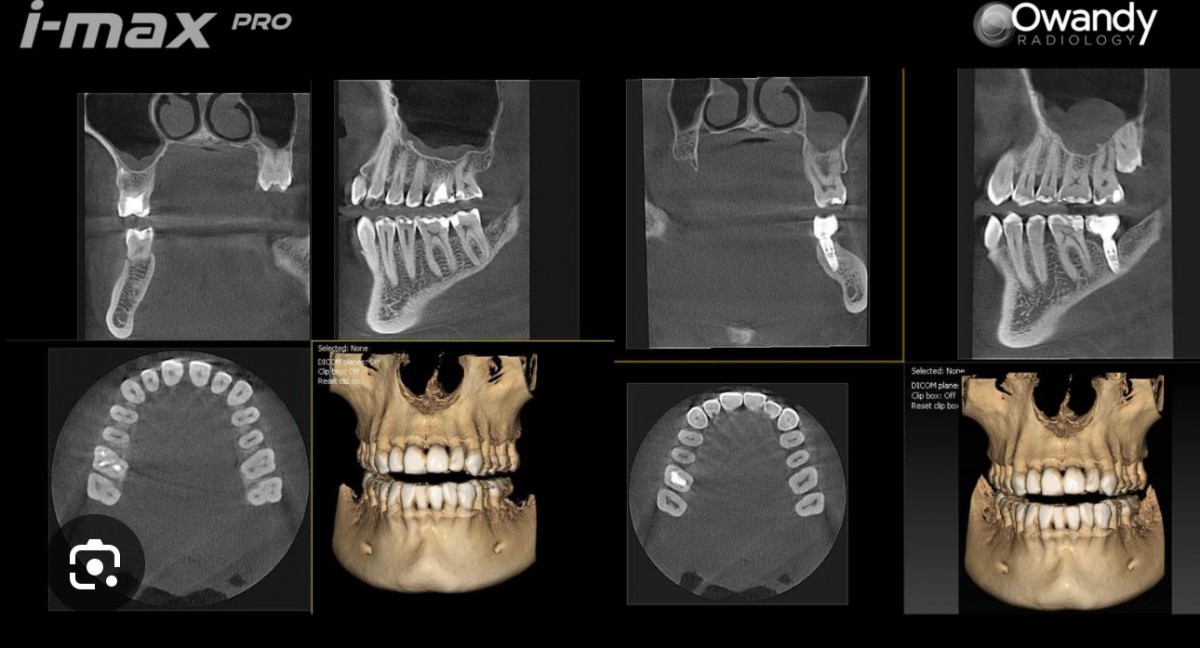

A clínica de medicina dentária Dr. Ricardo Cruz dispõe de um exame radiológico de elevada precisão, através do novíssimo equipamento de C.B.C.T., TAC 3D, o que permite realizar diagnósticos radiológicos com máximo rigor, através da tecnologia 3D, dando assim mais um importante passo tecnológico na elevada qualidade e segurança que oferece aos seus pacientes, na área da Cirurgia Oral e Implantologia.